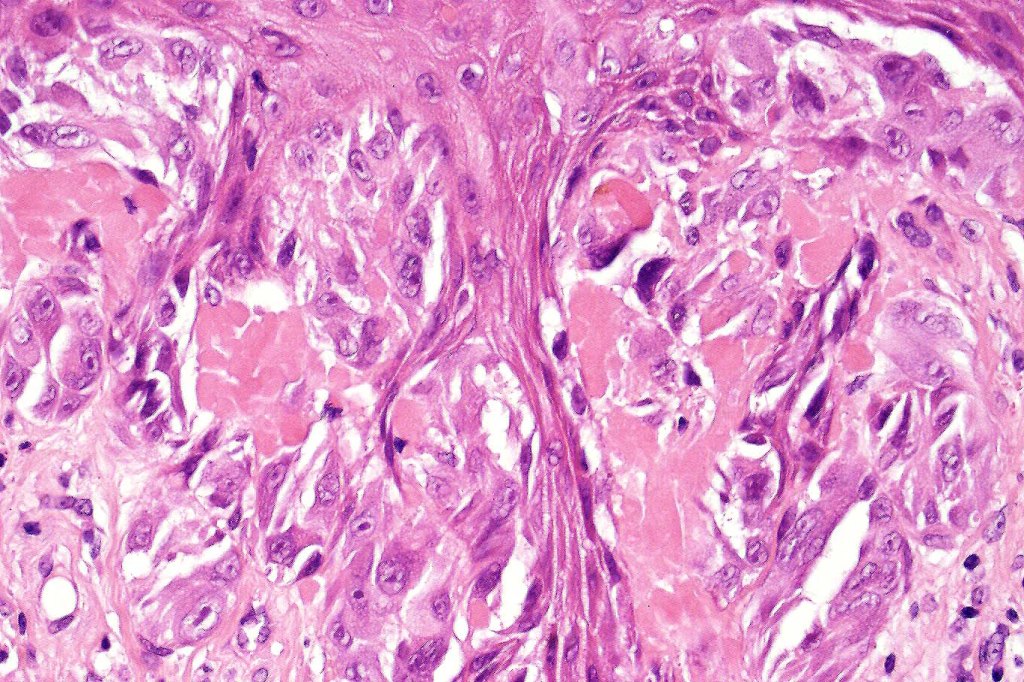

•Spindle cells have abundant cytoplasm and vesicular nuclei with small nucleoli

•Epithelioid cell variants often show greater pleomorphism and cells can frequently appear bizarre with abundant, sometimes ground glass cytoplasm and large vesicular nuclei with prominent eosinophilic nucleoli, multinucleate cells are often seen

•Intracytoplasmic pseudoinclusions commonly present in epithelioid cells